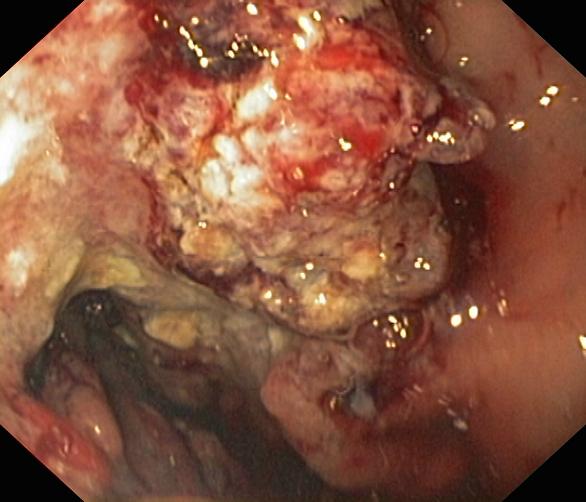

Nowotwory przewodu pokarmowego